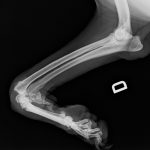

- Anchilosi Carpica Dx

- Artrodesi Pancarpale

- Anchilosi Carpica SX

- Margot